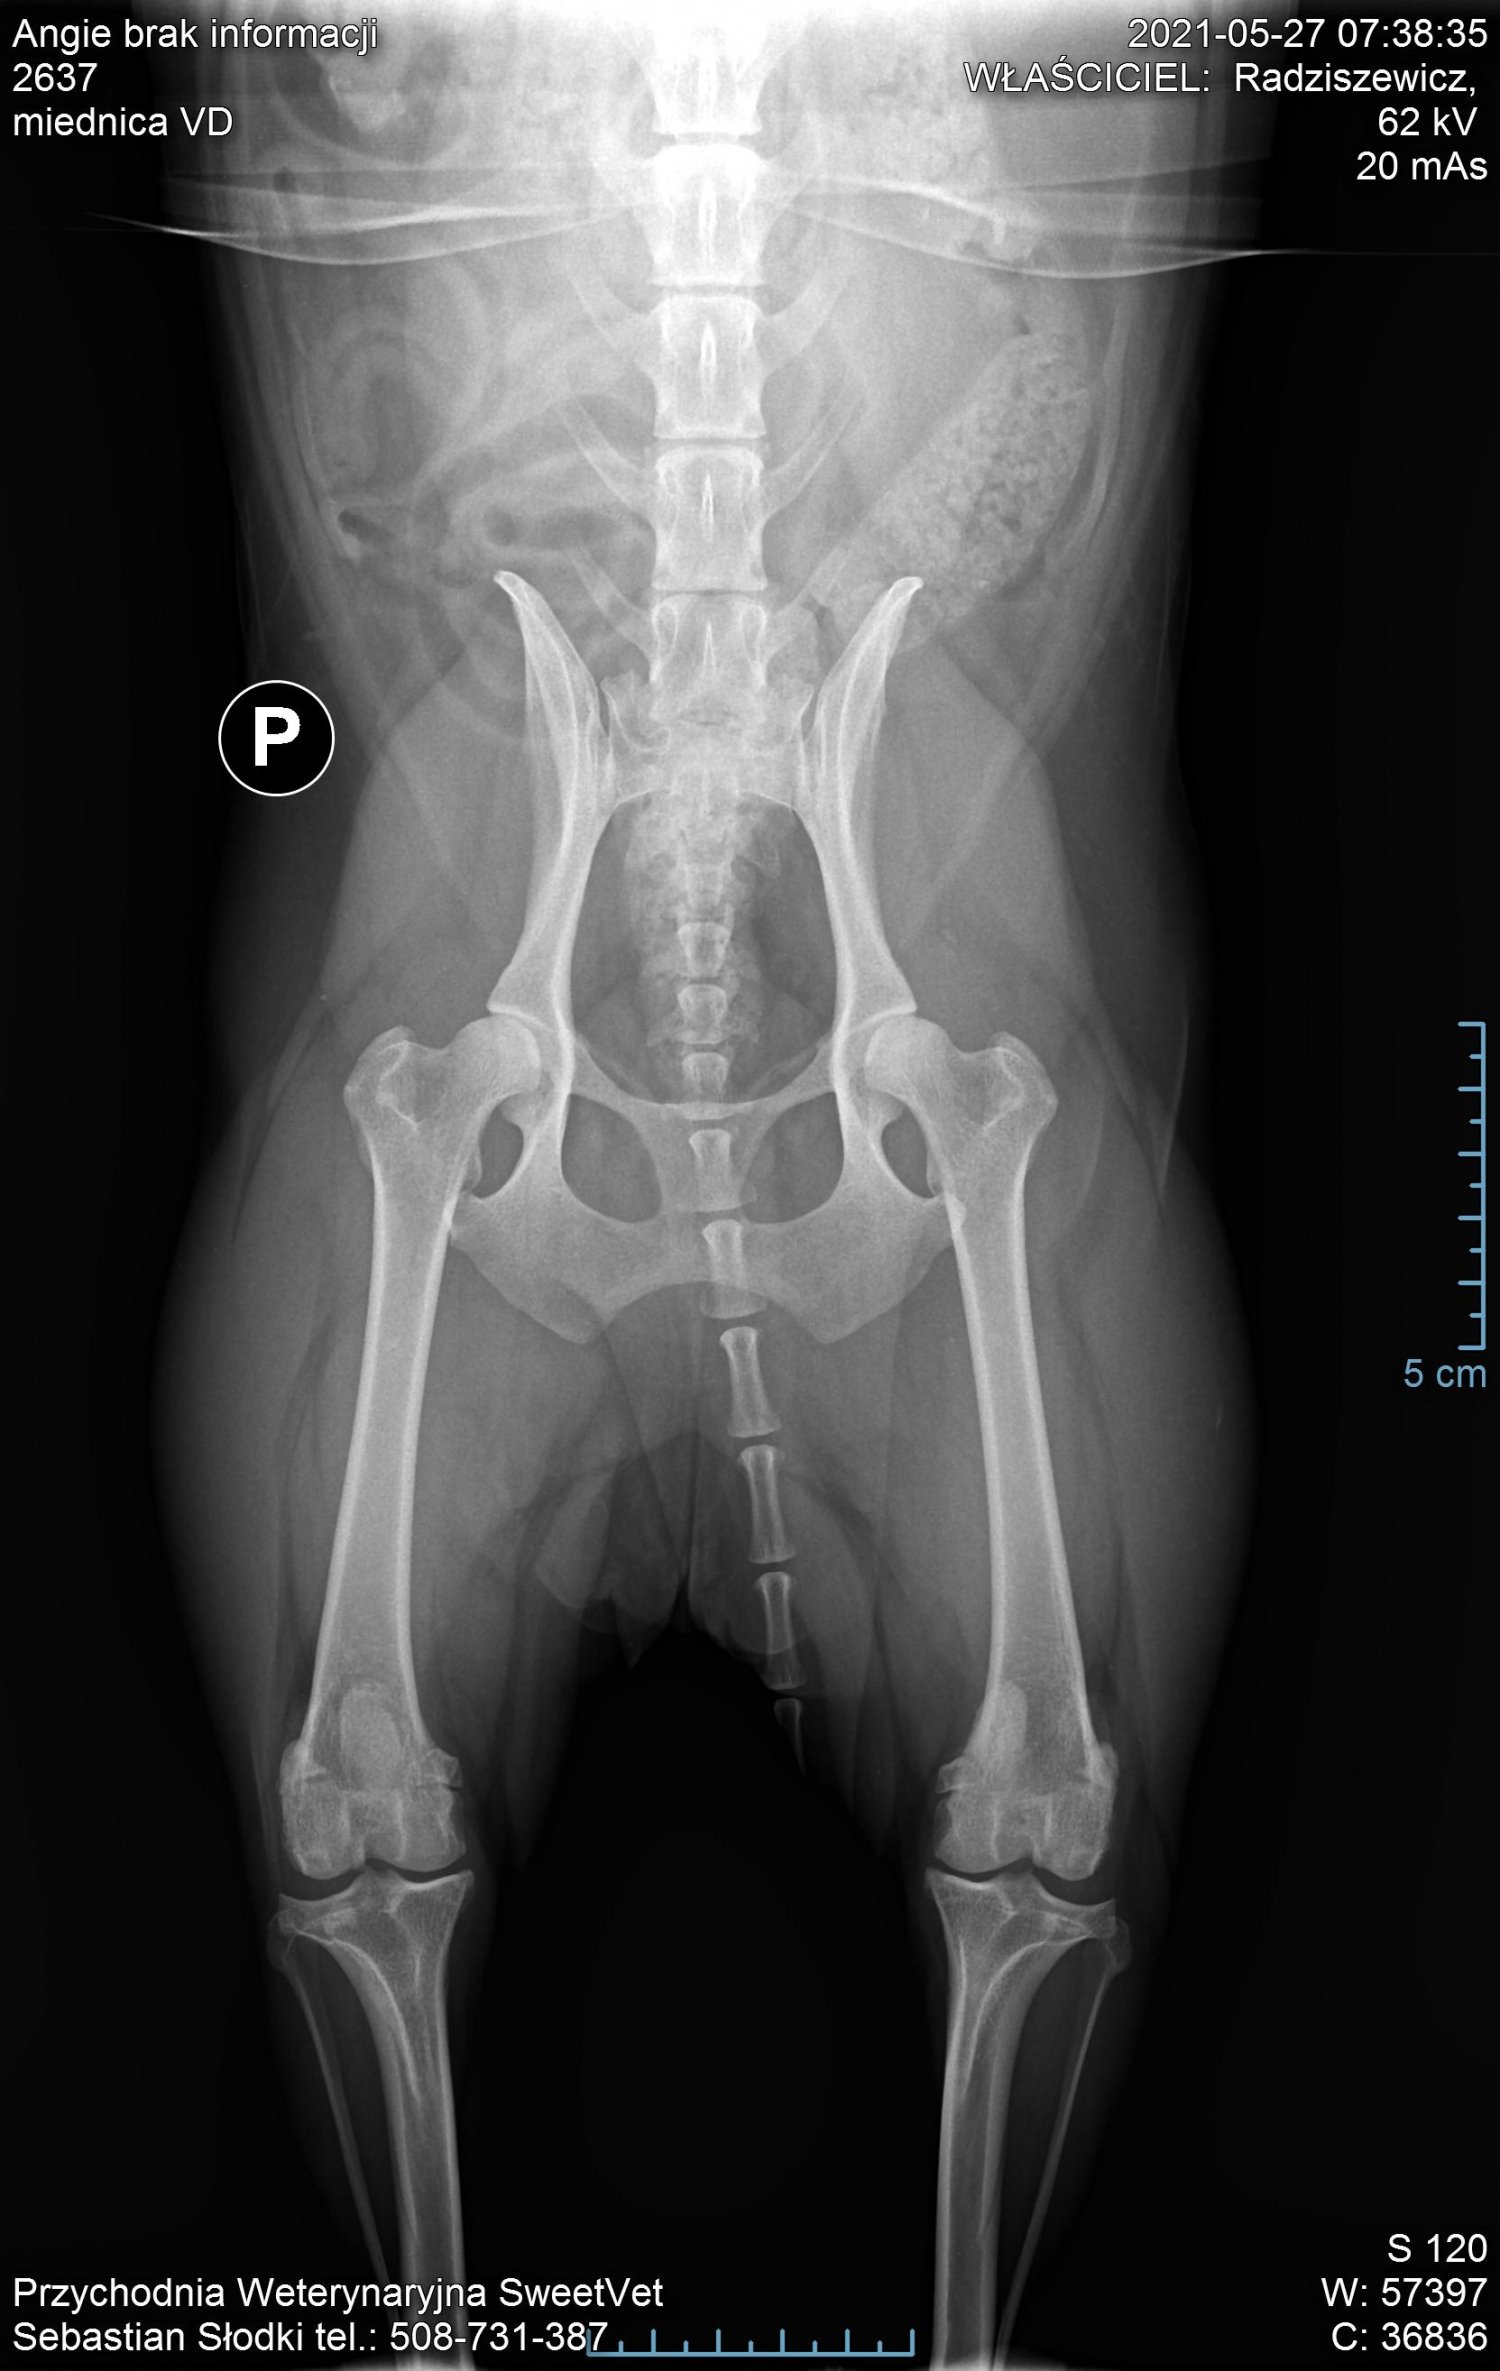

Na nasze szczęście wraz z początkiem maja dostaliśmy możliwość odbywania raz w tygodniu zajęć praktycznych na uczelni w Bydgoszczy. Jako, że mieliśmy opcję przyprowadzić na zajęcia własne zwierzęta i na nich ćwiczyć, zabrałam ze sobą moją Angie. Już na pierwszych zajęciach sunia pokazała dużą bolesność mięśni grzbietu. Tydzień później przy próbach masażu kończyn miednicznych psinka zareagowała agresywnie, od razu dała znać, że nie chce być tam dotykana. Na naszej uczelni przyjmuje fizjoterapeuta zwierząt, więc postanowiłam zaprowadzić tam swojego psa. Okazało się, że mięśnie tylnich łap i kręgosłupa są tak pospinane, że wywołują bardzo dużą bolesność. Przez odciążanie prawej (gorszej) łapki, mięśnie lewej są ciągle spięte, obolałe, przeciążone. Zaczęłyśmy działać przeciwbólowo i rozluźniająco poprzez laseroterapię, ultradźwięki i magnetoterapię. Pani zoofizjoterapeutka poleciła mi jeszcze zrobić dokładne zdjęcia RTG w jednej z bydgoskich klinik (ponieważ bez nich ciężko było wykluczyć bądź potwierdzić wskazania do zabiegu).

Nie zamierzałam się poddać i jeszcze w tym samym tygodniu pojechałam do kliniki Sweetvet na zdjęcia i konsultacje. Okazało się, że mimo tak dużej przestrzeni czasowej od wstępnej diagnozy stawy kolanowe Angie nie są w tragicznym stanie: lewa rzepka-zwichnięcie 2-ego stopnia, prawa- 3-ego. Zdjęcia RTG wykazały zwyrodnienia rzepki i głowy kości udowej w obu kończynach. Bez zabiegu sulkoplastyki i transpozycji guzowatości kości piszczelowej pogłębiające się z czasem zwyrodnienia doprowadzą do zerwania więzadeł. Doktor potwierdził, że Angie jako zdrowy pies, z dobrymi wynikami jak najbardziej nadaje się do operowania, tym bardziej, że teraz jesteśmy w stanie kolosalnie zmienić jej komfort życia.